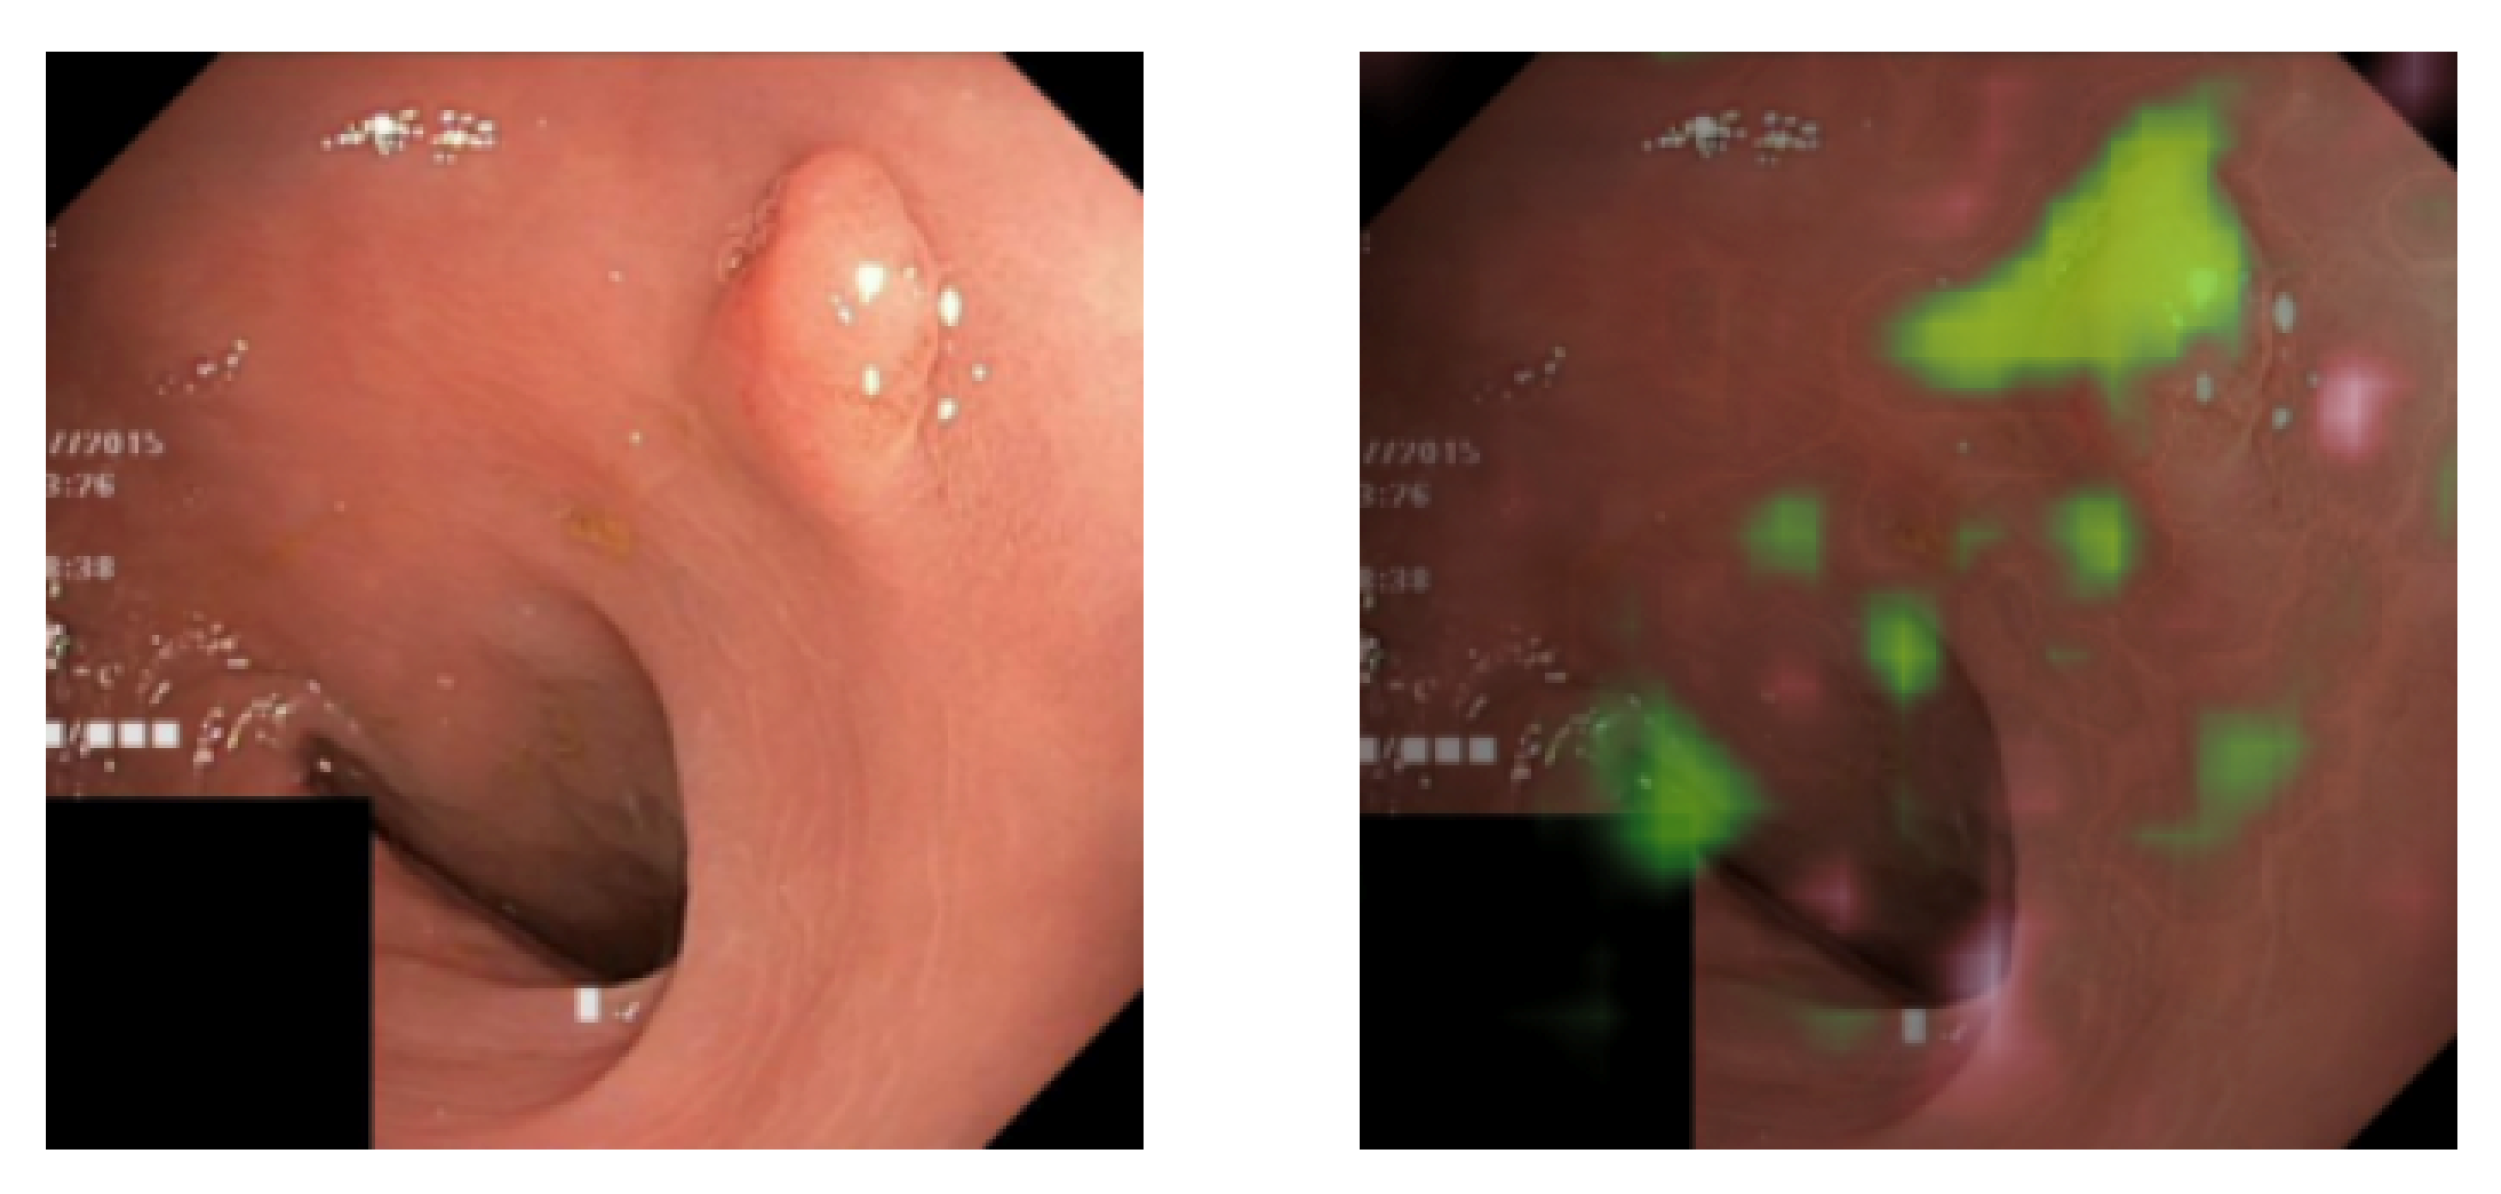

Dataset B contains 2056 images labeled as healthy in the HyperKvasir dataset and 2056 images, with half being real pathological images, in the form of polyps, and half being pseudo-real, in the form of blue shapes. We chose the blue ellipse because it resembles polyps in terms of size and shape, adding to the dataset’s challenge. Examples of healthy and pathological samples are shown in Figure 4. We see that half of the images in the pathological class consist of real polyps and half-blue shapes.

Figure 7 displays an image of a polyp (the small growth in the upper right corner) both with and without the overlaid explanation. The explanation highlights the most pronounced and expansive focus on the upper portion of the polyp, whereas the base of the polyp receives minimal attribution for the classification. Unlike the explanation for the pseudo-real image discussed earlier, this image identifies attribution in multiple areas. These areas, being less bright, suggest diminished importance. Whether these areas are medically significant cannot be determined without the input of a medical professional.

The images on the left side of Figure 10 display samples from the pathological class of Dataset B. The images on the right present the results after explanation weighting. Once again, we observe that the method efficiently isolates the pathological characteristics. However, the precision is slightly lower than for Dataset A. This outcome aligns with our expectations, given that classifying Dataset B is more challenging than Dataset A. This complexity arises because 50% of the pathological class in Dataset B comprises real pathologies (polyps).

Figure 4. Examples of images from Dataset B with images from the healthy class on the (left) and the pathological class on the (right). The pathological class features two pathologies: real polyps and blue shapes.

Figure 7. (Left) A real data sample of a polyp. (Right) The sample overlaid with its explanation.